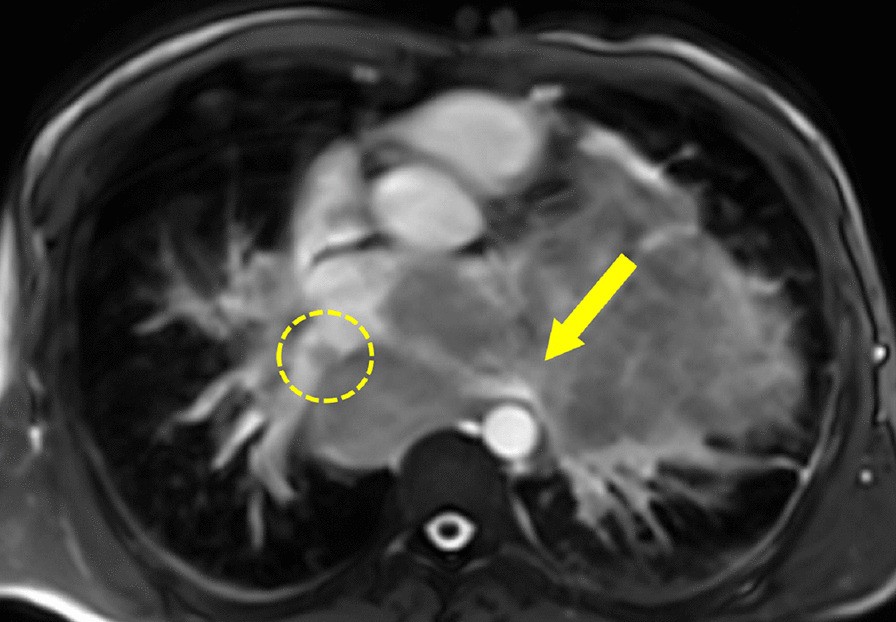

Fig. 14

From: Society for Cardiovascular Magnetic Resonance 2019 Case of the Week series

Case 4. Cine balanced steady state free precession (bSSFP) image shows the right pulmonary veins (yellow circle) and left pulmonary veins (yellow arrow) infiltrated by the mediastinal mass